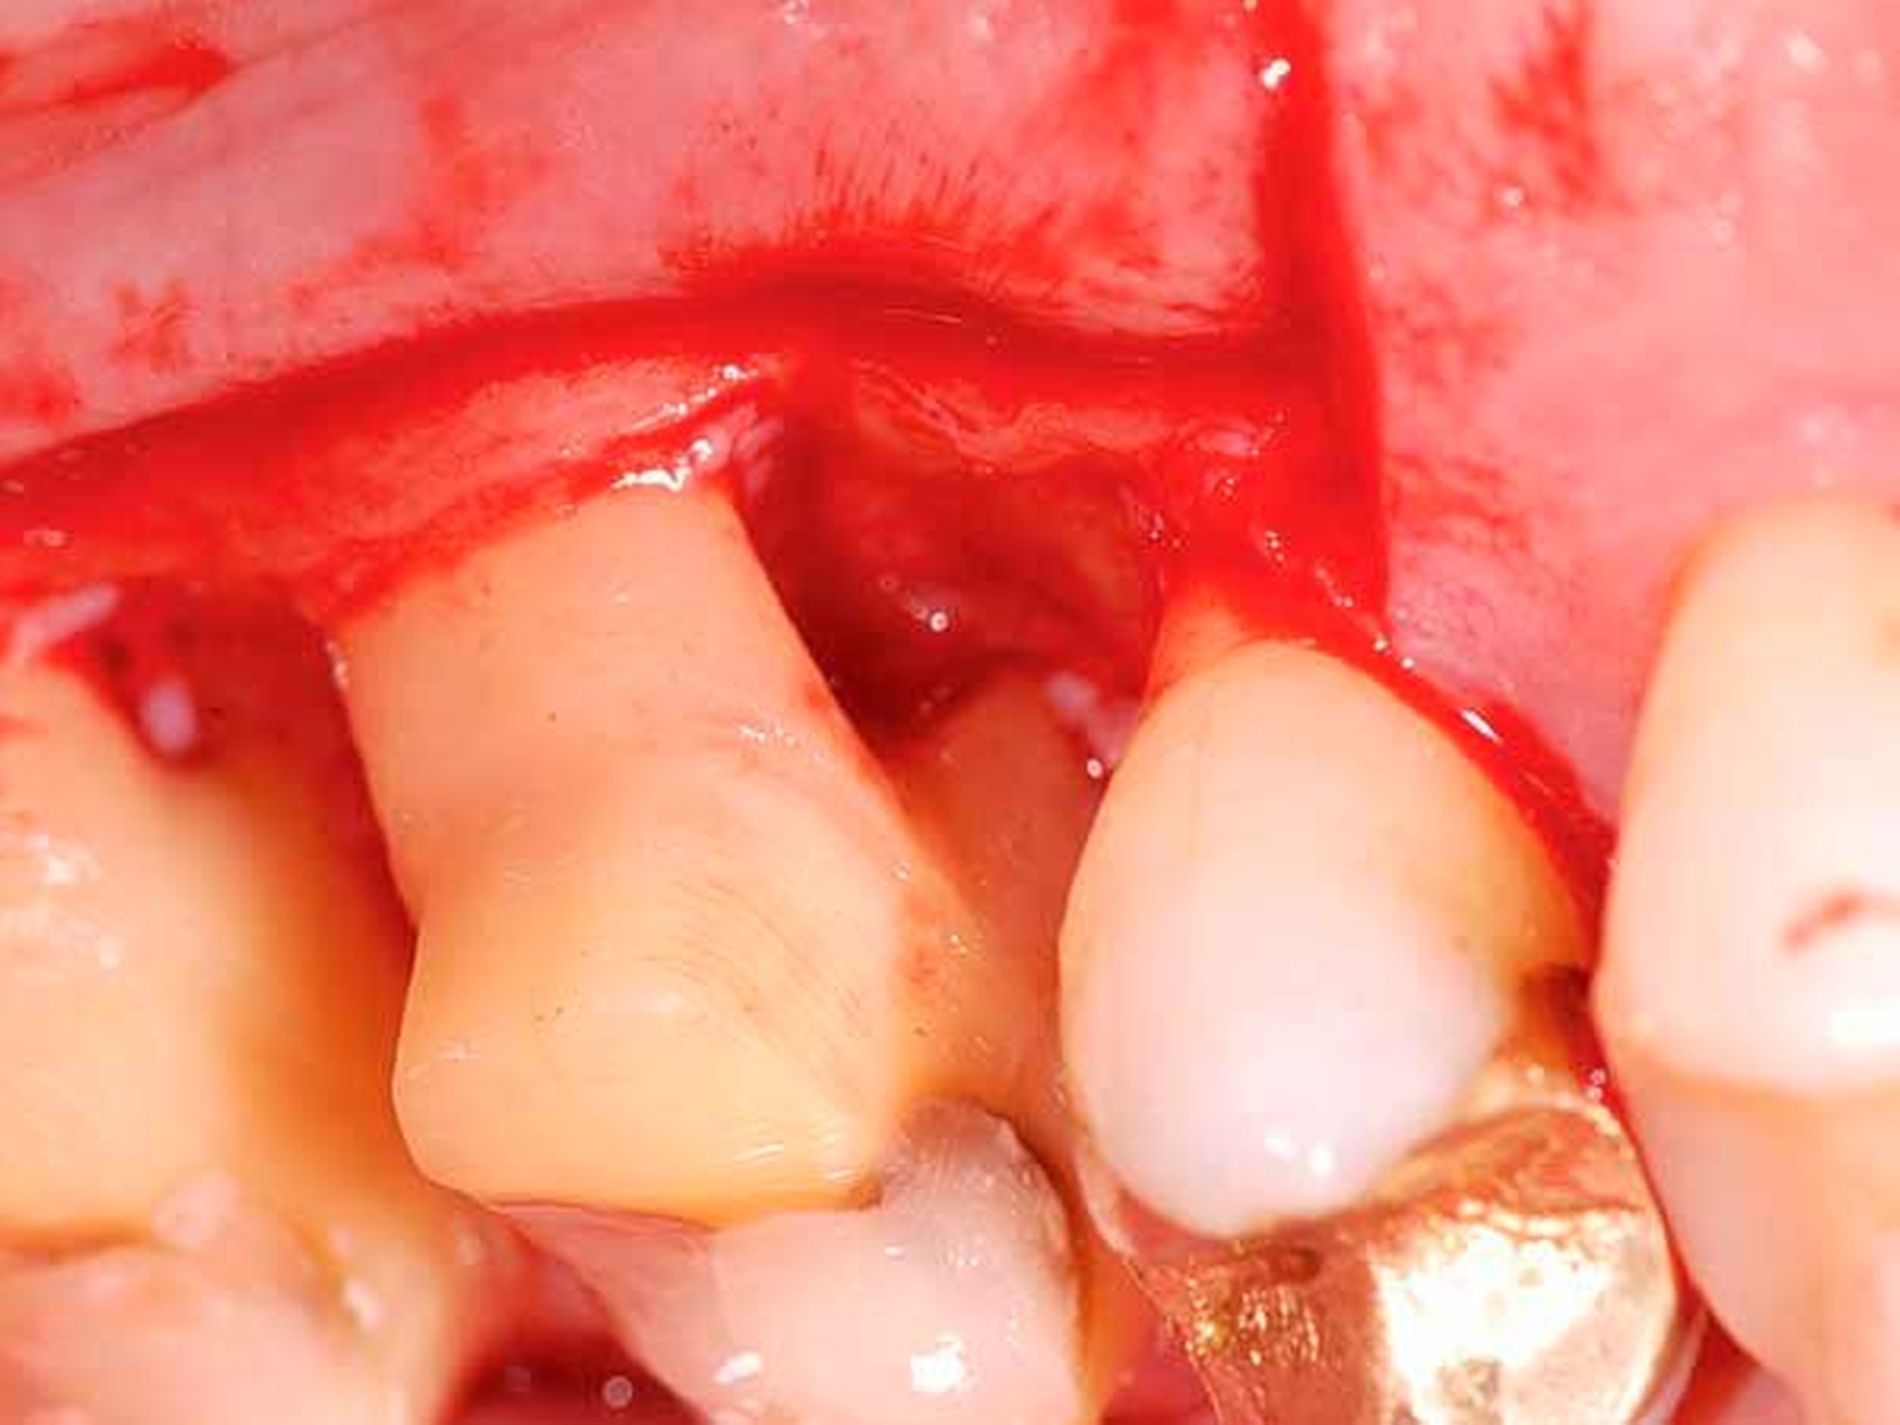

Reduktion der Sondierungstiefen (st) und Attachmentgewinne sechs und zwölf Monate nach nichtchirurgischer Therapie

Von großem Interesse sind derzeit weiterhin subgingival eingesetzte Pulver-Wasserstrahl-Geräte. Mit gering abrasivem Pulver, häufig auf Glycin-Basis, können damit schnell und gründlich Biofilme, aber keine mineralisierten Ablagerungen entfernt werden [Flemmig et al., 2012]. Das Verfahren hat daher seine Stärke im Bereich der unterstützenden Parodontitistherapie, wo in der Regel keine ausgeprägten Konkremente zu erwarten sind. Für einen denkbaren Einsatz während der subgingivalen Instrumentierung liegen noch keine ausreichenden klinischen Daten vor, insbesondere ist wahrscheinlich die dem Verfahren immanente Gefahr eines Luftemphysems bei dem in der ersten Behandlungsphase oft noch stark aufgelockerten Gewebe (vgl. Abbildung 1) noch deutlich erhöht.